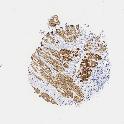

UROTHELIAL CANCER - Protein expressioni

A mouse-over function shows sample information and annotation data. Click on an image to view it in a full screen mode. Samples can be filtered based on level of antibody staining by selecting one or several of the following categories: high, medium, low and not detected. The assay and annotation is described here.

Note that samples used for immunohistochemistry by the Human Protein Atlas do not correspond to samples in the TCGA dataset.

Antibody stainingi

Antibody staining in the annotated cell types in the current human tissue is reported as not detected, low, medium, or high, based on conventional immunohistochemistry profiling in selected tissues. This score is based on the combination of the staining intensity and fraction of stained cells.

Each image is clickable and will lead to virtual microscopy that enables deeper exploration of all samples and also displays staining intensity scores, fraction scores and subcellular localization as well as patient and tissue information for each sample.

Antibody HPA008066

Antibody HPA017330

Antibody CAB000006

Staining

High

Medium

Low

Not detected

Intensity

Strong

Moderate

Weak

Negative

Quantity

>75%

75%-25%

<25%

None

Location

Nuclear

Cytoplasmic/membranous

Cytoplasmic/membranous,nuclear

Urothelial carcinoma, Low grade

Urothelial carcinoma, High grade